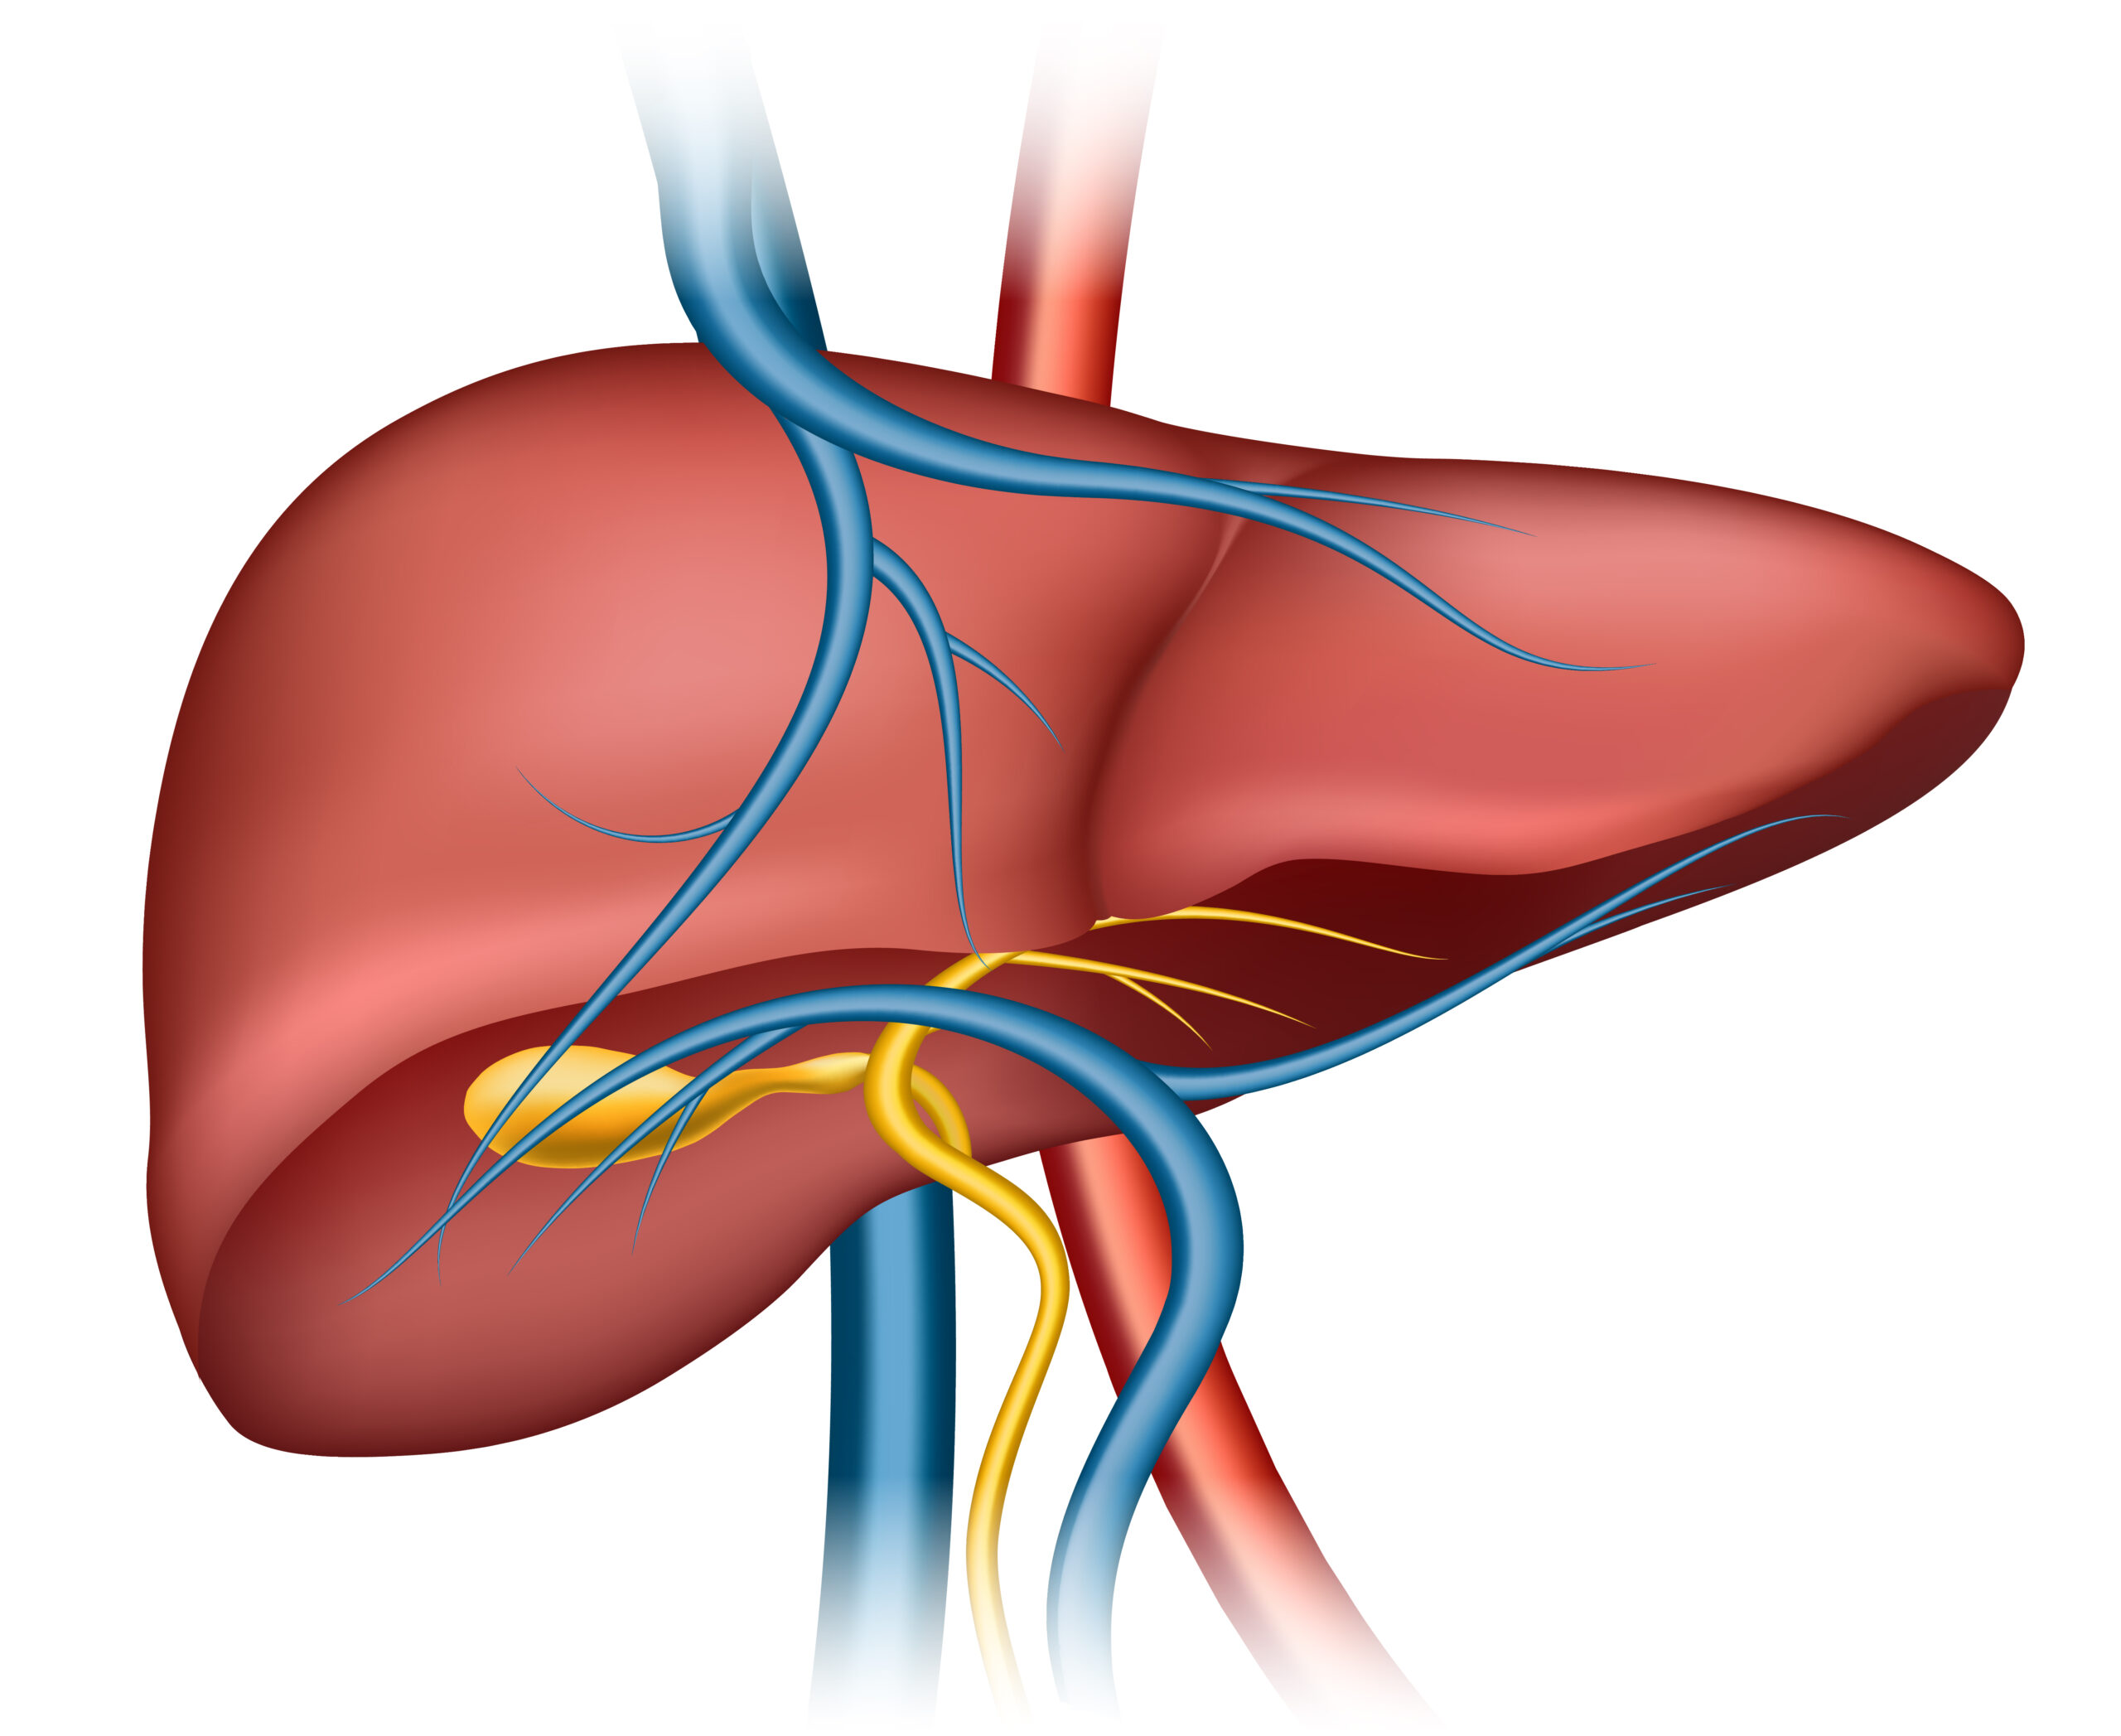

Department of Gastroliver Medicine

We provide advanced care for digestive and liver-related disorders. Our team of experienced gastroenterologists and hepatologists is dedicated to delivering personalized treatments using state-of-the-art technology. From diagnosis to treatment and recovery, we ensure the best possible care for our patients.